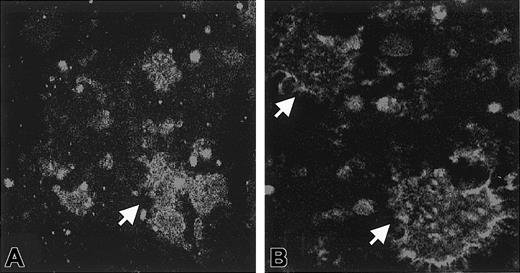

Effect of saponin permeabilization on immunofluorescence.

Washed platelets were incubated with Stx1, and aggregates formed in the medium. In experiments in which immunofluorescence was performed in the presence of saponin, FITC staining was noted inside the aggregates for all concentrations of Stx1 (A, 1 ng/mL Stx1). In experiments in which immunofluorescence was assayed without saponin, FITC staining was noted on the periphery of aggregates. This was demonstrated for all concentrations of Stx1 (B, 1 ng/mL Stx1). Arrows indicate aggregates. Aggregates were identified as platelets by counterstaining with antibody to CD41-PE (not shown). Magnification, × 1000.

After the incubation of platelets with Stx1, aggregates formed in the media. These aggregates contained platelets as identified by the presence of CD41 (Figure 1E). Marked uptake of Stx1 was demonstrated in these aggregates (Figure 1F). In separate experiments, Stx1B was incubated with platelets, and aggregates with prominent fluorescent Stx1B uptake were noted in the media (Figure 1G). Aggregate formation was noted for all concentrations of Stx1 and Stx1B used. Preincubation of Stx1B with monoclonal anti-Stx1 antibody inhibited the formation of platelet aggregates at all (Figure 1H) but the highest concentration of Stx1B. In immunofluorescence experiments in which the control antibody was used, there was no FITC-conjugated antibody uptake, but platelet aggregates were identified by the presence of CD41. In experiments in which immunofluorescence was assayed without saponin, FITC staining was noted on the periphery of aggregates but not within them (Figure2).